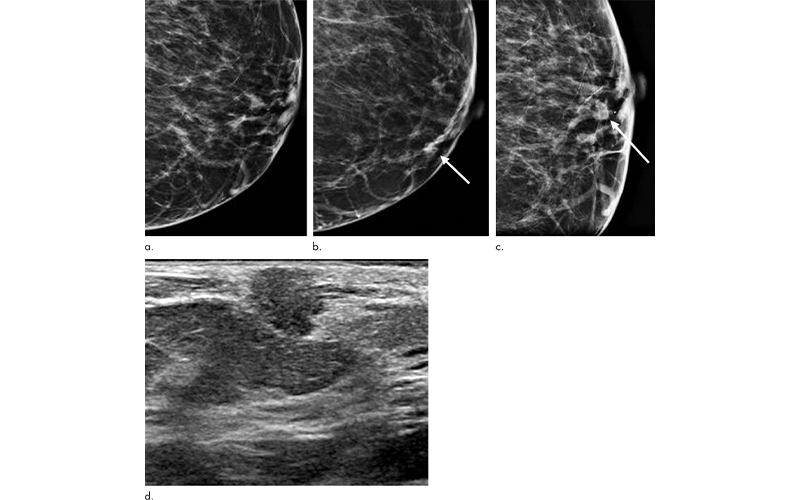

Breast cancer screening with digital breast tomosynthesis (DBT) offers significant advantages over digital mammography, including improved cancer detection and lower false negative rates, according to a study in Radiology.

Analysis showed that screening with DBT improved sensitivity and specificity for breast cancer and identified more invasive cancers with fewer nodal or distant metastases.

The results also showed advantages for DBT in imaging women with mammographically dense breasts. Recall rates were significantly lower in both heterogeneously dense breasts and extremely dense breasts in the DBT group compared to digital mammography.

“We also saw significantly higher cancer detection rates with DBT in women with heterogeneously dense breasts compared to digital mammography,” Dr. Durand said. “With women who have extremely dense breasts, the cancer detection was higher, but not significantly so, which makes sense. You need a bit of fat to provide contrast to the fibroglandular tissue in order to detect abnormalities, whether you are using DBT or digital mammography. This highlights a group of women who would benefit from supplementary screening.”